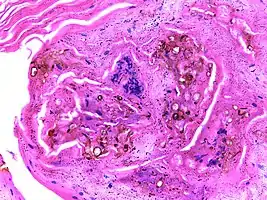

Micrograph of chromoblastomycosis showing sclerotic bodies

The most informative test is to scrape the lesion and add potassium hydroxide (KOH), then examine under a microscope. (KOH scrapings are commonly used to examine fungal infections.) The pathognomonic finding is observing medlar bodies (also called muriform bodies or sclerotic cells). Scrapings from the lesion can also be cultured to identify the organism involved. Blood tests and imaging studies are not commonly used.

On histology, chromoblastomycosis manifests as pigmented yeasts resembling "copper pennies".[9]

Special stains, such as periodic acid schiff and Gömöri methenamine silver, can be used to demonstrate the fungal organisms if needed.